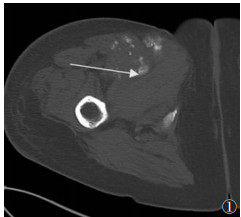

中期病变23例,X线(23例)、CT(16例)、MRI(12例)及SPECT/CT(4例)阳性率均为100.0%。X线或CT表现为软组织肿块周边高密度骨化影,14例呈絮状、片状或点状(图 1,2a,3a),9例呈蛋壳样骨化,肿块中央密度较低(图 4)。MRI示肿块呈分层状改变,最外侧(外层)呈条带状T1WI高信号、T2WI低信号(骨化);中间区(中间层)T1WI呈等信号、T2WI呈高信号;中心区域(内层)T1WI、T2WI均呈高信号;肿块外围呈边界不清的T2WI和STIR脂肪抑制高信号(水肿)(图 2b,2c)。SPECT/CT表现为病灶整体显像剂摄取,病灶中央摄取程度高于周围(图 3b)。

| 图 1 女,55岁,右侧大腿骨化性肌炎(中期)。CT横轴位扫描图像,显示右侧大腿前侧软组织内呈絮状、片状骨化,沿肿块周围分布(箭头) |